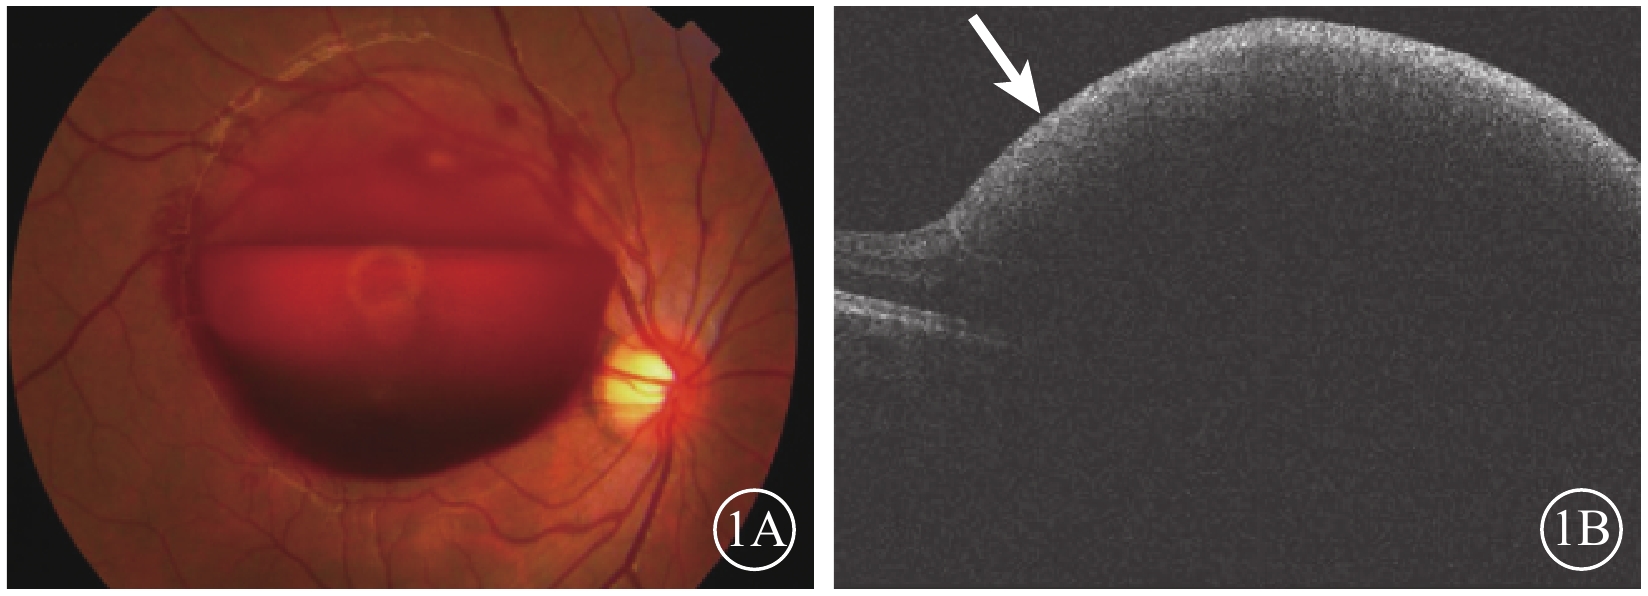

患者男,20歲。因右眼視力突然下降伴眼前黑影遮擋于2015年11月30日來我院就診。患者訴1周前右眼視力突然下降伴眼前黑影遮擋,視物呈紅色;無眼紅、眼痛、畏光、流淚。既往雙眼視力正常;視力下降前有咳嗽史,視力下降當天曾用力排便。否認飲酒、外傷史以及高血壓病、糖尿病、血液病等全身系統性疾病。血壓:113/63 mmHg(1 mmHg=0.133 kPa);眼科檢查:右眼視力數指/15 cm,不能矯正;左眼視力0.3,矯正視力1.2。右眼眼壓12 mmHg,左眼眼壓14 mmHg。左眼眼前節及眼底檢查未見異常。右眼眼前節檢查未見異常。眼底視盤邊界清楚,色澤淡紅;黃斑區類圓形隆起視網膜前出血,直徑約6個視盤直徑(DD),其余視網膜平復,未見出血及滲出(圖1A)。熒光素眼底血管造影(FFA)檢查,黃斑區前半月形出血遮蔽熒光灶,其余視網膜未見明顯異常熒光。光相干斷層掃描(OCT)檢查,黃斑視網膜前強反射,遮擋其后組織結構回聲(圖1B)。實驗室血尿常規、生物化學及凝血機制等檢查結果無異常。診斷:右眼Valsalva視網膜病變。

圖1

右眼彩色眼底、OCT像。1A. 彩色眼底像,黃斑區視網膜前6 DD大小出血區,遮蔽黃斑;1B. OCT像,視網膜前強反射信號(白箭),其下方視網膜組織反射信號消失

圖1

右眼彩色眼底、OCT像。1A. 彩色眼底像,黃斑區視網膜前6 DD大小出血區,遮蔽黃斑;1B. OCT像,視網膜前強反射信號(白箭),其下方視網膜組織反射信號消失

患者男,20歲。因右眼視力突然下降伴眼前黑影遮擋于2015年11月30日來我院就診。患者訴1周前右眼視力突然下降伴眼前黑影遮擋,視物呈紅色;無眼紅、眼痛、畏光、流淚。既往雙眼視力正常;視力下降前有咳嗽史,視力下降當天曾用力排便。否認飲酒、外傷史以及高血壓病、糖尿病、血液病等全身系統性疾病。血壓:113/63 mmHg(1 mmHg=0.133 kPa);眼科檢查:右眼視力數指/15 cm,不能矯正;左眼視力0.3,矯正視力1.2。右眼眼壓12 mmHg,左眼眼壓14 mmHg。左眼眼前節及眼底檢查未見異常。右眼眼前節檢查未見異常。眼底視盤邊界清楚,色澤淡紅;黃斑區類圓形隆起視網膜前出血,直徑約6個視盤直徑(DD),其余視網膜平復,未見出血及滲出(圖1A)。熒光素眼底血管造影(FFA)檢查,黃斑區前半月形出血遮蔽熒光灶,其余視網膜未見明顯異常熒光。光相干斷層掃描(OCT)檢查,黃斑視網膜前強反射,遮擋其后組織結構回聲(圖1B)。實驗室血尿常規、生物化學及凝血機制等檢查結果無異常。診斷:右眼Valsalva視網膜病變。

圖1

右眼彩色眼底、OCT像。1A. 彩色眼底像,黃斑區視網膜前6 DD大小出血區,遮蔽黃斑;1B. OCT像,視網膜前強反射信號(白箭),其下方視網膜組織反射信號消失

圖1

右眼彩色眼底、OCT像。1A. 彩色眼底像,黃斑區視網膜前6 DD大小出血區,遮蔽黃斑;1B. OCT像,視網膜前強反射信號(白箭),其下方視網膜組織反射信號消失